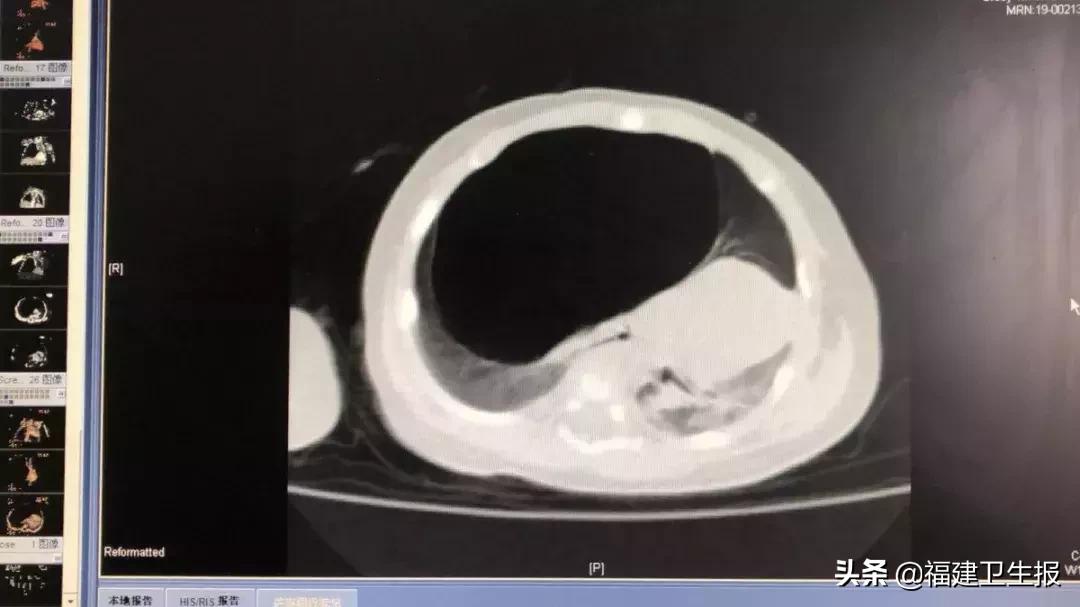

检查发现,洋洋的右肺内肿起了一个直径达10厘米的囊肿,它侵占了洋洋的左右两个肺,若不及时切除,洋洋随时都会被死神带走。

原来,这个肺囊肿打洋洋在娘胎里就存在了,只不过在母亲怀孕期间,产前诊断提示这个囊肿的直径只有3厘米。

谁知,就在发病当天的半天时间里,这个肺囊肿就肿成了皮球大小。